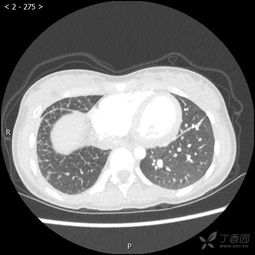

我叫小丽(化名),是一个普通的中学生。在我读初中的时候,命运跟我开了一个残酷的玩笑。一次体检中,医生发现我的左肺长了一个肿瘤,经过进一步检查,确诊为肺癌。这对于我和我的家人来说,无疑是一个晴天霹雳的消息。

为了阻止病情恶化,医生建议尽快进行手术。考虑到我的年龄和身体状况,他们决定切除左肺。这是一场风险极高的手术,但为了活下去,我没有丝毫犹豫。手术当天,父母紧紧握着我的手,给予我无限的支持和鼓励。